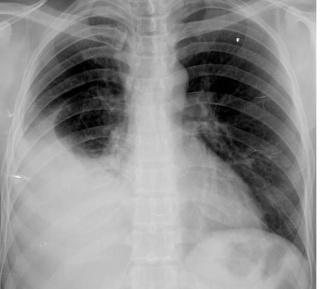

El diagnóstico del un derrame pleural se realiza por lo general mediante radiografía, donde los signos son visibles cuando el volumen es mayor de 75 ml., teniendo en cuenta que los valores normales de líquido están entre los 5 y 15 ml.